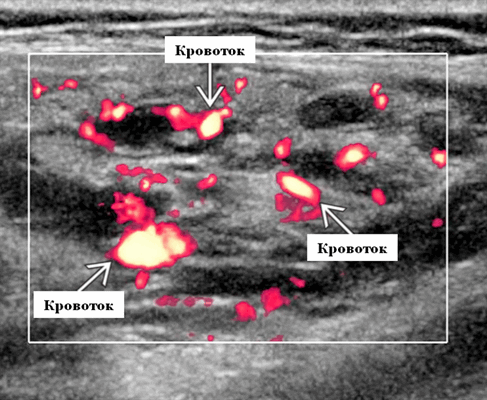

Лучший диагностический критерий. Неоднородно гипоэхогенное поражение, синусоидальные сосудистые пространства, движение вперед и назад в реальном времени ± эхогенные флеболиты. Выраженный сигнал потока на цветном или энергетическом доплеровском режиме. Монофазный низкоскоростной поток на импульсном доплеровском режиме

Результаты ультразвукового исследования. УЗИ в серошкальном режиме. Большинство сосудистых венозных гемангиом (80%) выглядят неоднородно гипоэхогенными. Большие анэхогенные сосудистые пространства видны менее чем в 50% случаев, серпигинозные и синусоидальные. Поражения с небольшими сосудистыми каналами могут казаться эхогенными (из-за множества акустических границ, отражающих звук). Определить пределы образования бывает трудно, так как компоненты поражения могут быть изоэхогенными в околоушной паренхиме и незаметно смешиваться. Внутрипросветное движение эхо-сигналов при УЗИ в реальном времени, представляющее медленный сосудистый кровоток. Характерны эхогенные флеболиты с задним акустическим затенением. Сообщается, что они присутствуют только в 20% ВСМ. Иногда поражается вся околоушная железа, имитируя диффузную или инфильтративную патологию. Целесообразность склеротерапии оценивается соотношением сосудистых пространств к эхогенной матрице

Импульсный допплер. Монофазный, низкоскоростной поток может иногда обнаруживаться в анэхогенных и гипоэхогенных пространствах, представляющих открытые сосуды со значительным кровотоком. Отсутствие допплеровского сигнала при медленном кровотоке или тромбировании

Цветной допплер. Выраженный цветной доплеровский сигнал присутствует в областях, где поток значительный. Используйте фильтр для стенок сосудов и низкую частоту повторения импульсов (PRF) для увеличения доплеровской чувствительности. Отсутствует допплеровский сигнал при медленном кровотоке или тромбировании. Доплеровский сигнал потока изменяется различными маневрами. В поверхностных участках доплеровский сигнал может быть остановлен прямым сжатием датчика над поражением. Сигнал потока может иногда быть усилен маневром Вальсальвы или дистальным сжатием, но последнее трудно выполнить в области лица.

Венозные мальформации на УЗИ

Венозные мальформации также являются низкопотоковыми сосудистыми мальформациями и состоят из эктатических венозных структур. Хотя венозные пороки развития являются врожденными поражениями, они могут не стать симптоматическими до поздних дней жизни пациентов и иногда выявляются на УЗИ случайно. При физическом обследовании венозные пороки развития могут быть синими, прохладными и сжимаемыми и могут увеличиваться в размерах после маневров, направленных на увеличение венозного давления. Венозные мальформации могут проявляться в виде локализованной массы или в виде множественных инфильтративных извилистых варикозных сосудов, которые пересекаются с несколькими тканевыми плоскостями. Ультразвуковое исследование венозных мальформаций обычно демонстрирует сжимаемое, гипоэхогенное и гетерогенное поражение мягких тканей.

Флеболиты могут наблюдаться у небольшого числа пациентов на УЗИ. При импульсном допплеровском обследовании может быть идентифицировано однофазное низкоскоростное течение. В некоторых случаях сосудистый поток внутри очагов может быть слишком медленным, чтобы его можно было обнаружить при ультразвуковом исследовании. Как и при лечении лимфангиом, чрезкожная склеротерапия с ультразвуковым контролем является первым методом лечения венозных мальформаций.